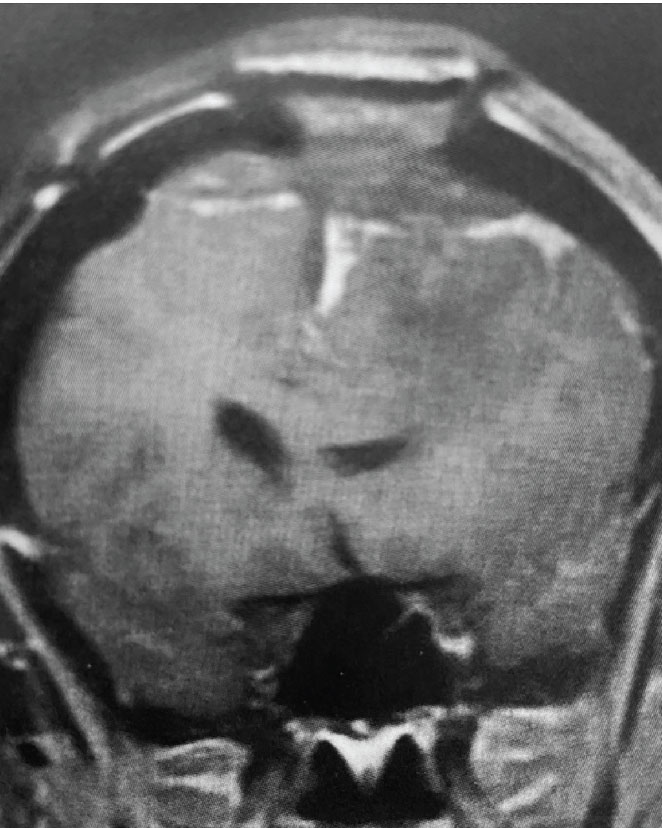

Fig 2. B) Post-operative, post-contrast, coronal MRI.

Treatment: Given the size and location of this tumor, the best treatment was surgical removal. Surgery was performed by Dr. Michael Brisman. A craniotomy exposed the tumor along the convexity as well as the superior sagittal sinus. The tumor was removed, as was the involved convexity dura and the affected segment of the sagittal sinus. Removed dura and skull were replaced with duraplasty (with artificial dura) and a titanium mesh cranioplasty.

Outcome: The patient did very well and made a full recovery.